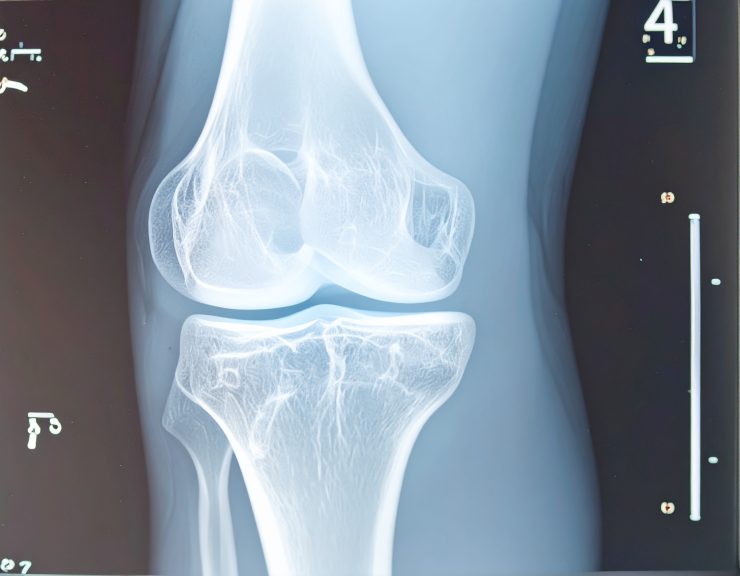

La mise en place d’une prothèse du genou représente une solution chirurgicale envisagée en dernier recours pour soulager des douleurs articulaires chroniques, améliorer la mobilité et restaurer une qualité de vie acceptable lorsqu’une arthrose avancée, une polyarthrite rhumatoïde ou un traumatisme articulaire ont détérioré l’articulation au point de nuire au quotidien. Bien que cette intervention soit de plus en plus courante et généralement efficace, elle n’est pas dénuée de contraintes, de limites ou d’effets secondaires. Le recours à une arthroplastie du genou peut transformer radicalement la vie du patient, mais il implique aussi une période de réadaptation importante, des ajustements fonctionnels, des restrictions physiques et parfois des complications plus ou moins sévères selon les cas. Chaque individu réagit différemment à cette opération orthopédique majeure, et il est crucial de bien comprendre les inconvénients potentiels d’une prothèse totale ou partielle du genou avant de prendre une décision éclairée. Ces effets indésirables peuvent être d’ordre mécanique, biologique, fonctionnel ou psychologique, et nécessitent un suivi médical rigoureux sur le long terme pour prévenir l’apparition de douleurs persistantes ou d’échecs prothétiques.